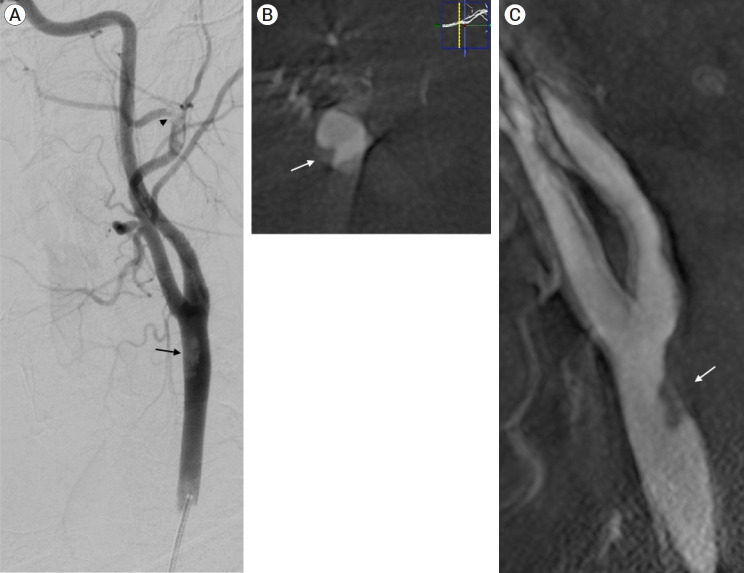

The carotid web (CW), an intimal variant of fibromuscular dysplasia (FMD), is recognized as a cause of stroke and with a high-risk of stroke recurrence. Other names are carotid-bulb atypical FMD, carotid (bulb) diaphragms and it is described like a shelf of tissue from the posterior wall of the carotid bulb. Here we present a case of a young patient with recurrent stroke, with no other risk factors that was diagnosed with a common CW.